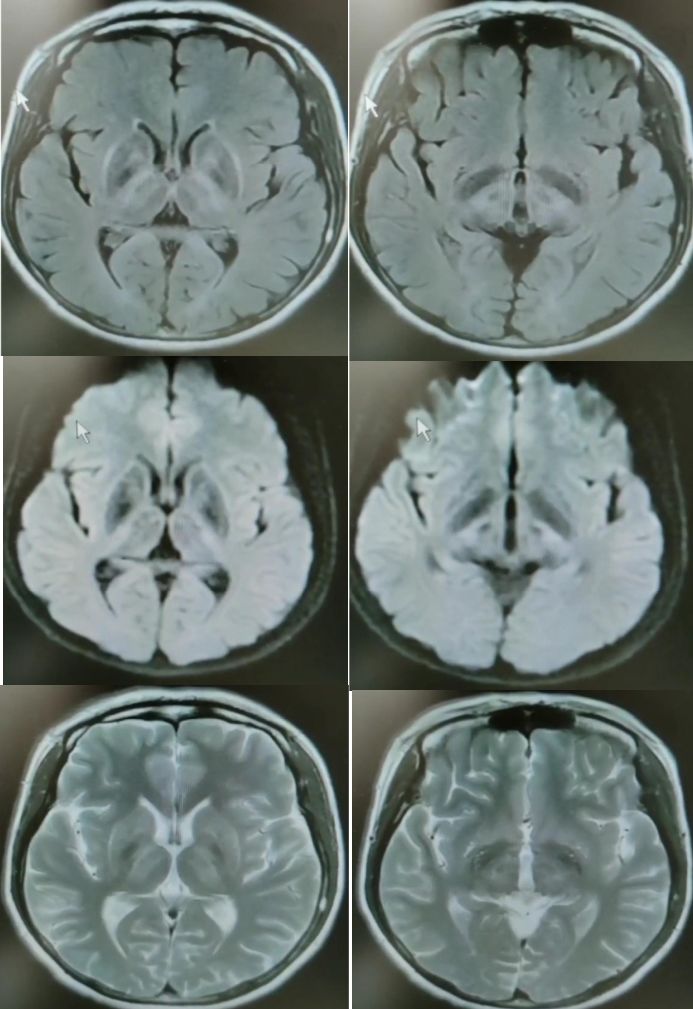

30岁女性,言语不清3年。

答案:肝豆状核变性。又称Wilson’病(WD),是一种常染色体隐性遗传的铜代谢障碍性疾病。主要是由于铜离子异常大量沉积于肝、脑、肾等策划,从而导致全身多系统多器官的损害,以神经系统症状、精神症状、眼部损害、肝脏损害等为主。神经系统最突出的症状是锥体外系症状,包括震颤、构音障碍、肌张力障碍、手足徐动症、共济失调等。构音障碍表现为声音低沉、含糊或嘶哑、缓慢或断续,严重时发不出声,是舌、唇、咽、喉和下颌肌肌张力增高所致。而肝脏的表现通常为肝功能损害、肝硬化、门脉高压症等,一般年轻患者居多。MRI表现为壳核、尾状核头和苍白球在T2WI上呈低信号,齿状核和红核亦可见T2WI为低信号。还可有不同程度的脑萎缩,如两侧壳核对称性裂隙,豆状核、尾状核、大脑皮质、脑干和小脑的萎缩。大小熊猫征为Wilson病的典型特征。